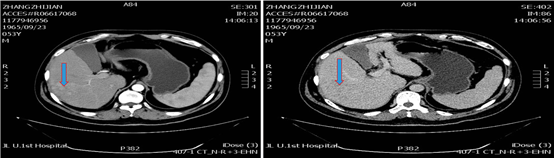

2019年1月17日(术后1个月)入院复查,影像学见疑似复发病灶。                         图片

图:影像学检查(2019-01-17)

遂予肝动脉化疗栓塞(TACE)治疗,行数字减影血管造影(DSA)可见肝右叶多个结节状肿瘤染色,明确肝左、右动脉分支为肿瘤供血动脉,判定为外科术后复发。